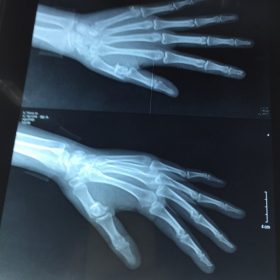

e. Chấn thương

· Điều trị, phẫu thuật chấn thương xương, khớp

MỘT SỐ HÌNH ẢNH PHẪU THUẬT CỦA KHOA